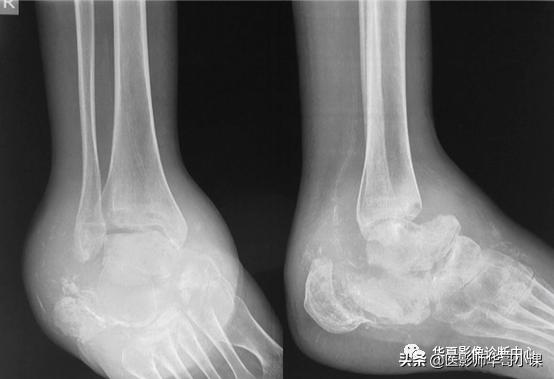

- 足和踝

- 病因:长期难以控制的糖尿病、梅毒

- 软组织肿胀、发热、红斑

- 部位:通常由中足开始

- 血管钙化

- 距(骨)舟(骨)的移位伴中足骨病变

- 鉴别诊断:骨髓炎、脓毒性关节炎(通常局限于一个关节)

跟骨破坏,距骨舟骨关节脱位,近端跗骨吸收,跗关节紊乱,软组织肿胀,动脉钙化。